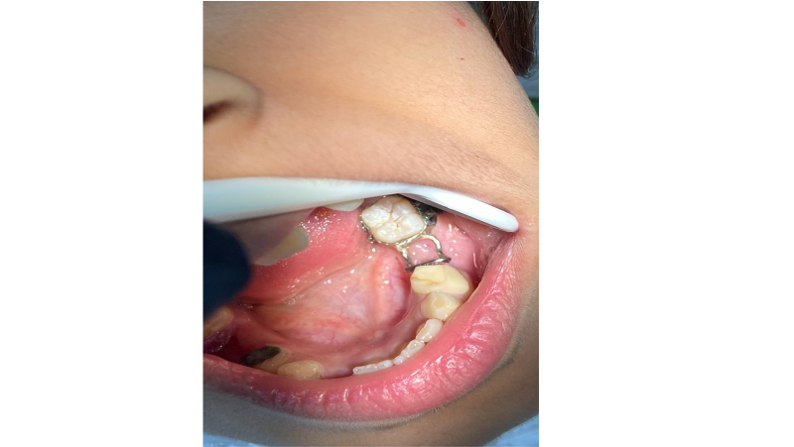

جانب من عمل SPACE MANTAINER لمريض في عيادة طب أسنان الاطفال .

19 Nov

2022/11/19 اقرأ المزيد